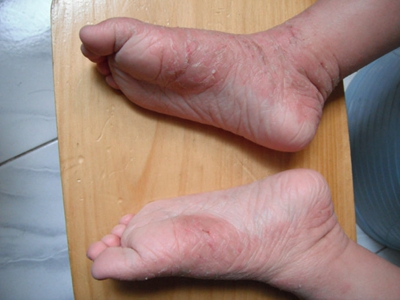

儿童期特应性皮炎发生于2岁以上的儿童,绝大多数由婴儿特应性皮炎延续发病,也有少部分儿童是在本期初发,多有丘疹、糜烂、苔藓样变等皮损表现。

儿童期特应性皮炎多呈现典型的湿疹改变,皮损渗出减少、干燥,以丘疹、糜烂和苔藓化为特点,特别好发于四肢、口周等处,最大特点是发生于两肘窝、两腘窝。皮损有轻度苔藓化,呈现糜烂面,少量渗出,自觉剧烈瘙痒。